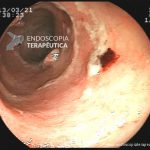

- Doença de Crohn em remissão – cicatriz